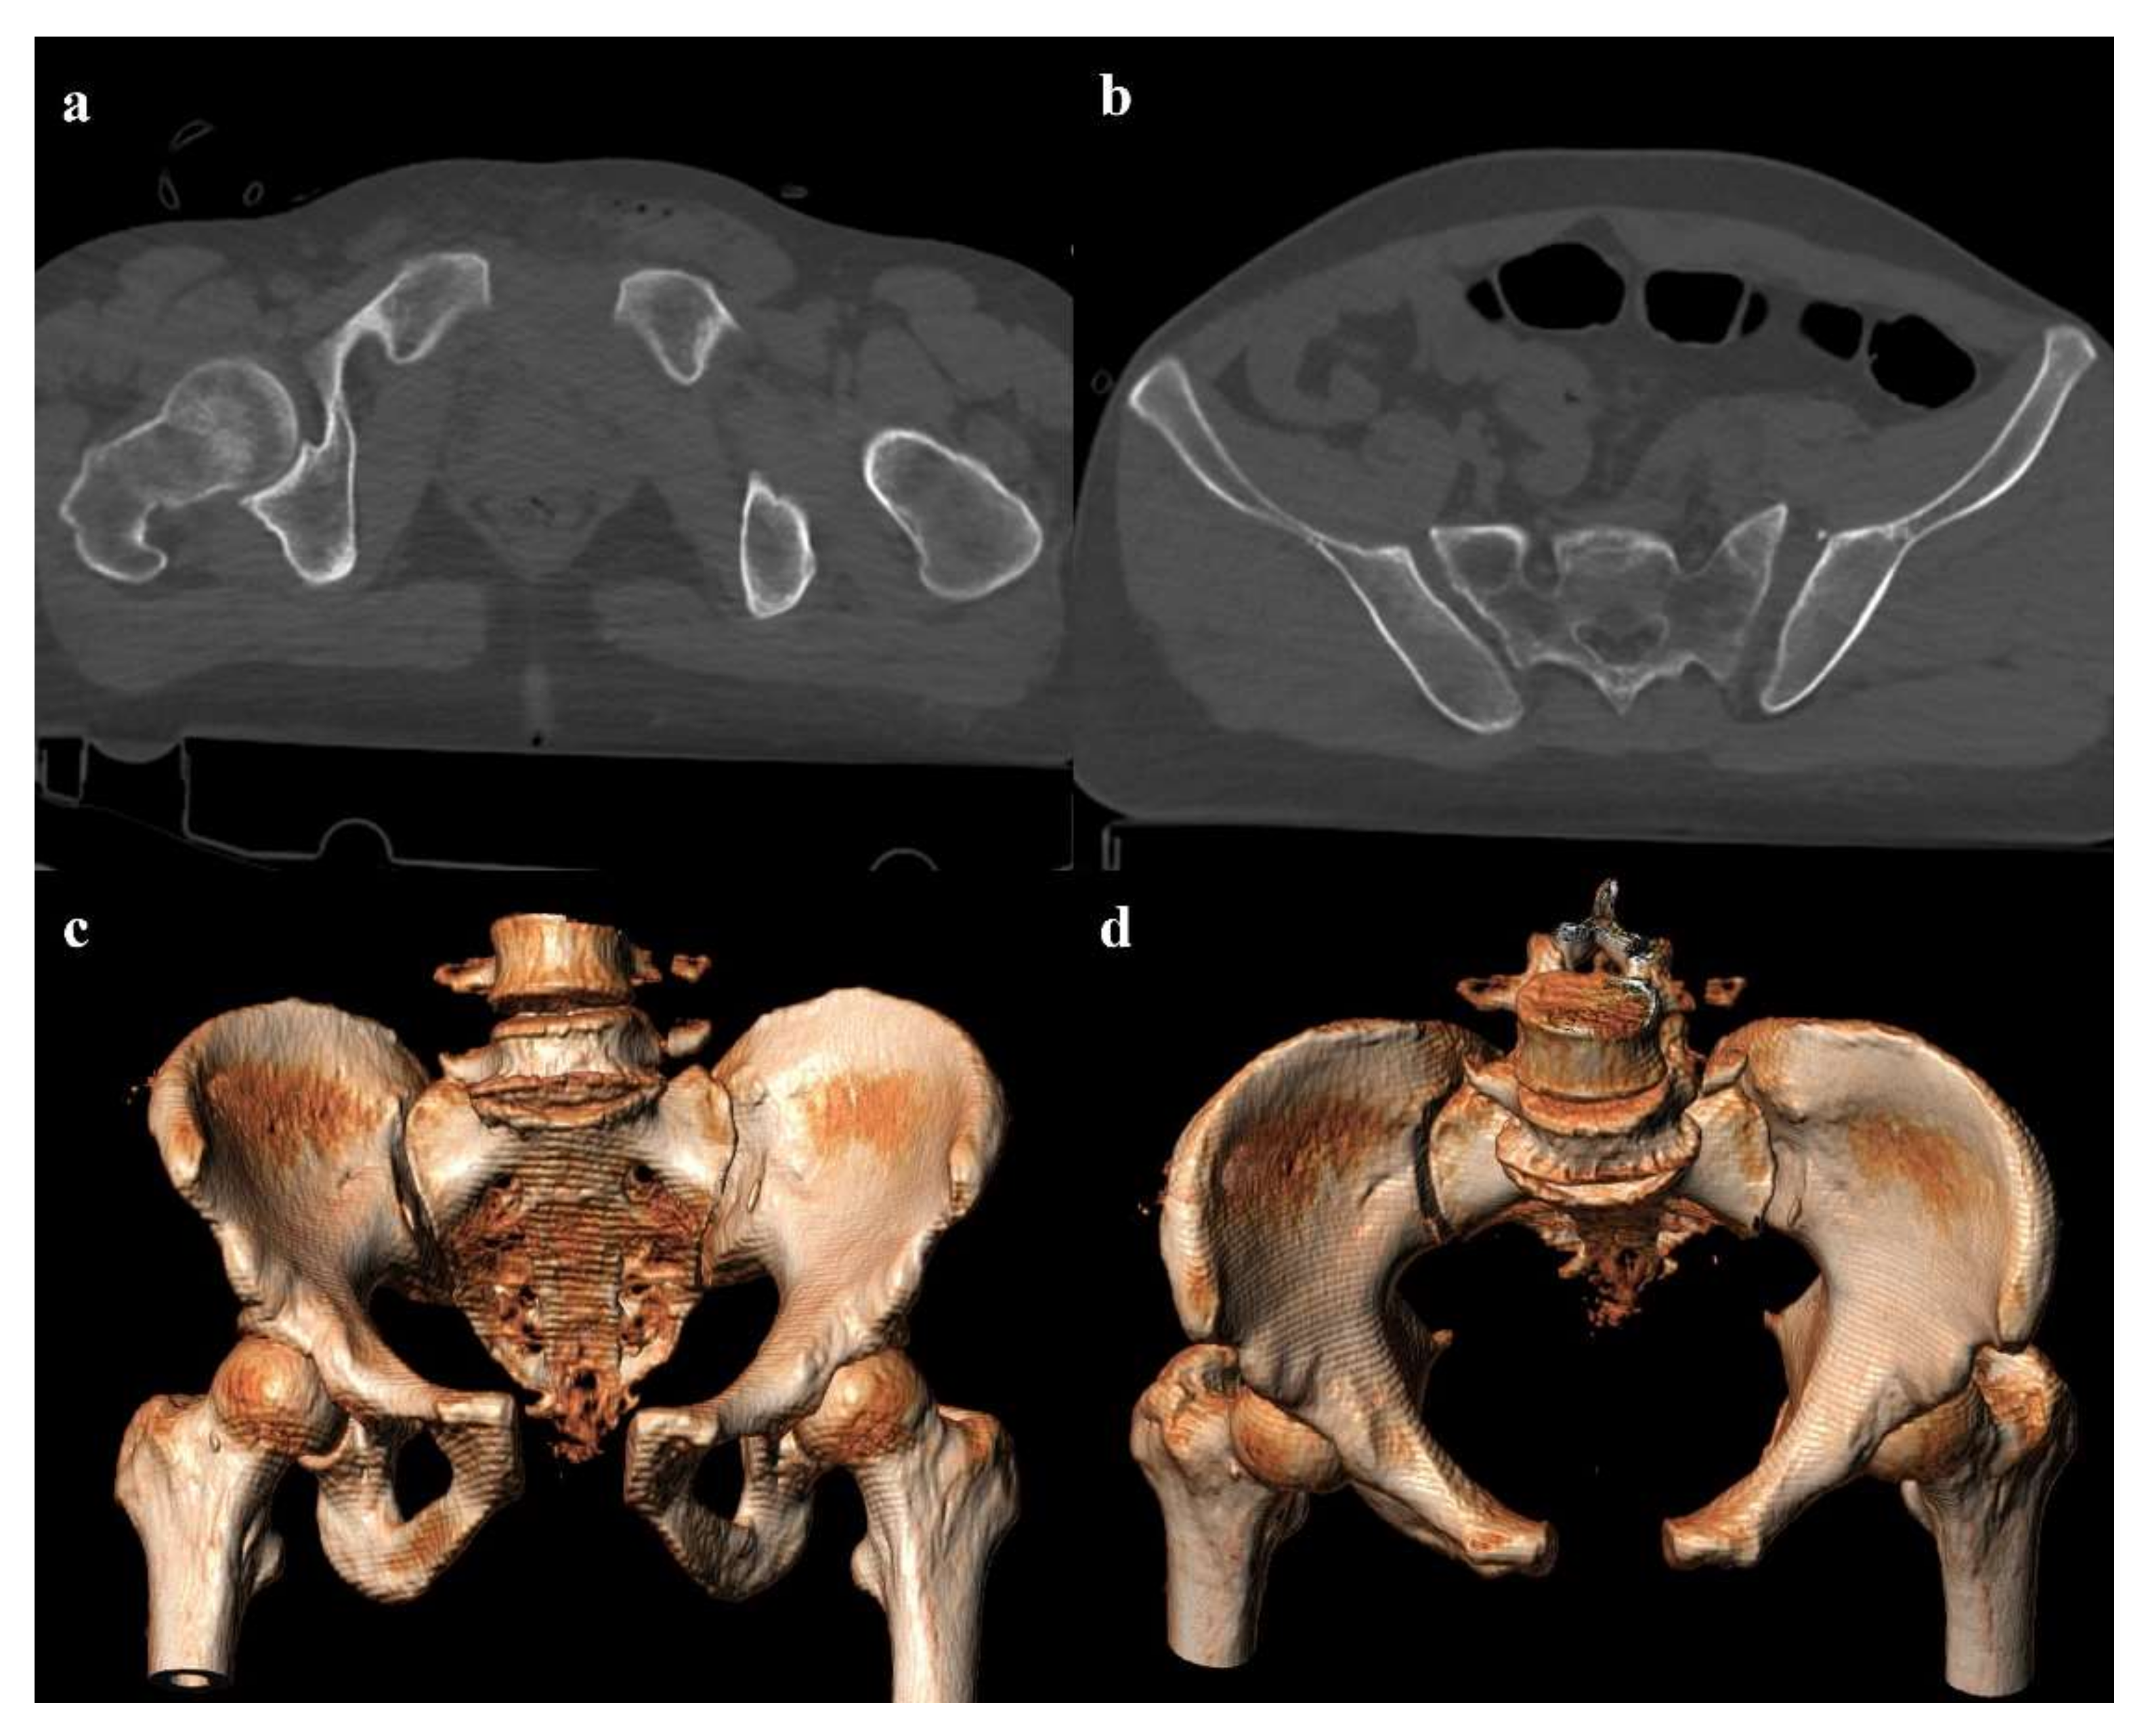

• Grade 2: grade 1 fractures, iliac wing fracture, posterior sacroiliac joint diastasis (Figure 2). Lateral compression grade 2 injuries have a rotational instability and require a stable internal fixation [3]. In these lesions, an adjunctive temporary external fixation is useful [3].

• Zone I: the fracture is located in the sacral wing, lateral to the neuroforamina (Figure 2). In 6% of cases, there is an impingement of L5 or S1 nerve root.

Figure 2. Lateral compression fracture, type 2. Axial CT images show a fracture of both the sacral wings (arrows in (a)), without the involvement of the neuroforamina (zone I). There is also fracture of the iliac wing on the right side (arrow in (b)), and ipsilateral fracture of the superior and inferior pubic branches (arrowheads in (c,d)).